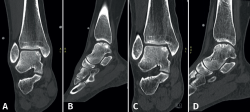

Fixation techniques are primarily applied to osteochondral lesions of the talus (OLTs) with fragmentary morphology. Consensus was that, for these techniques to be technically feasible, the lesion fragment should have a diameter of at least 10 mm and a depth of 3 mm(39). However, successful fixation has also been described for smaller lesions in studies using cortical bone pegs(40).

For acute displaced fragmentary lesions, fixation should be considered as the initial treatment(4). This should be performed as soon as possible to maximize healing potential and avoid further intra-articular damage(39). For chronic lesions, fixation can be applied when non-operative management is unsuccessful. As fixation techniques can provide superior subchondral bone healing(41), as well as preserving the overlying hyaline cartilage, it should be considered as the primary surgical treatment option when feasible.

Several fixation techniques using different materials have been described, including Kirschner wires, metal screws, bio-absorbable screws, bone pegs and/or fibrin glue(42,43,44,45). Fixation techniques may be performed arthroscopically when technically possible. The less invasive nature of arthroscopic fixation is theoretically advantageous. The most decisive factor for the possibility of arthroscopic fixation being the location/accessibility of the lesion. To achieve an adequate and stable fixation, the fragment needs to be fixated perpendicular to the talar dome. Therefore, the lesion must be located relatively anterior on the talar dome for arthroscopic fixation to be feasible(11). If arthroscopic fixation is not technically possible, it can also be performed as an open technique.

One specific surgical fixation technique is the Lift, Drill, Fill and Fix (LDFF) procedure(45). In this technique, the osteochondral lesion is visualized, and a beaver knife is used to create a flap. The flap is then lifted to allow for debridement and microfracturing of the subchondral bone. Cancellous bone, typically harvested from the distal tibial metaphysis, can be placed in the bed of the flap. Finally, the osteochondral flap is repositioned and fixed using bio-absorbable compression screws, chondral darts or bone pegs.

Fixation techniques have shown clinical and radiological success in 8 out of 10 patients, also maintaining their success in the long term (Figures 5 and 6). As these techniques preserve the hyaline cartilage and provide superior healing of the subchondral bone, they are advantageous over other surgical treatment options for OLTs, when feasible(39,41).